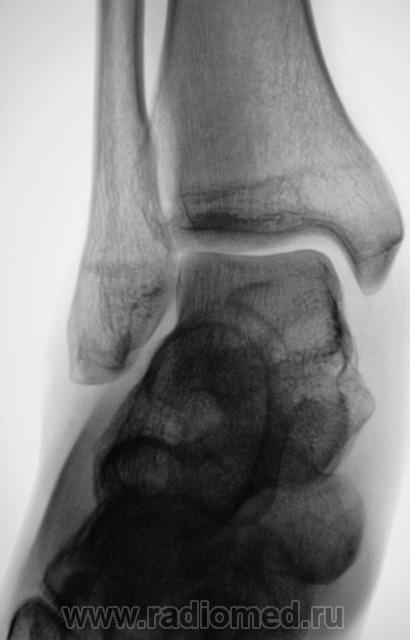

Пол пациента: Мужской пол Тип патологии: Другое Область исследования: Скелетно-мышечная система Методы исследования: Rg Пациент направлен врачом хирургом в рентгеновский кабинет по поводу болей в голеностопном суставе. Произведена рентгенография голеностопного сустава Ваше мнение уважаемые коллеги? Tue, 06/10/2009 - 22:21 #1 Ермолаев Offline Last seen: 8 years 11 months ago Joined: 07.02.2009 - 16:33 Posts: 670 Думаю, что имеет место артроз голеностопного сустава и таранно-ладьевидного, таранно-пяточного суставов. Только это следствие, а причина мне видится в наличии повреждения дистального межберцового синдесмоза. dok Tue, 06/10/2009 - 22:48 #2 В.Б. Серов Offline Last seen: 1 month 2 weeks ago Joined: 16.07.2008 - 10:15 Posts: 1361 Дугообразная деформация костей, с линейными зонами перестройки, плоскостопие. Полный комплект дефектов Зри в корень!

Думаю, что имеет место артроз голеностопного сустава и таранно-ладьевидного, таранно-пяточного суставов. Только это следствие, а причина мне видится в наличии повреждения дистального межберцового синдесмоза.

Дугообразная деформация костей, с линейными зонами перестройки, плоскостопие. Полный комплект дефектов